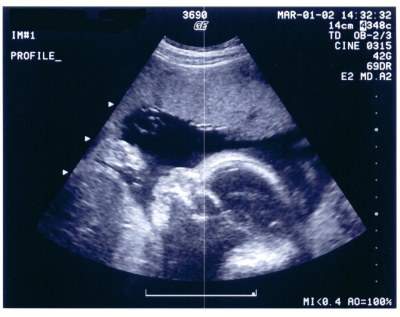

هنا جنينك في الاسبوع السابع عشر